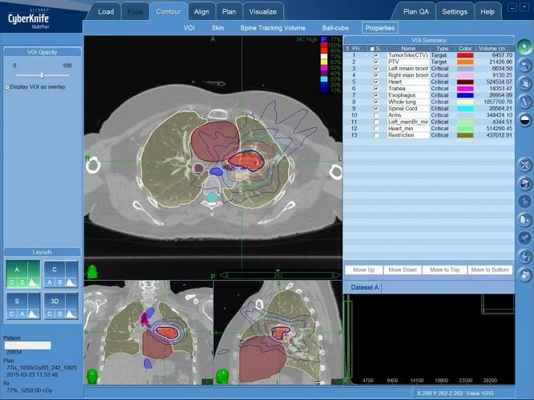

Радиохирургическая система КиберНож

Если злокачественная опухоль выявлена на ранней (бессимптомной) стадии, и еще не достигла значительных размеров, высокого эффекта можно добиться при применении радиохирургического лечения мезотелиомы плевры на КиберНоже.

Преимуществом такого выбора является высочайшая точность подачи губительного для опухоли ионизирующего излучения. При этом требуемая доза будет равномерно доставлена КиберНожом в каждую точку небольшой опухоли, не допуская недостаточного облучения, что довольно часто становится причиной радиорезистентности опухоли (наблюдается при лучевом лечении на устаревших кобальтовых аппаратах либо при недостаточном внимании к планированию лечения на линейных ускорителях).

Радиохирургическое лечение мезотелиомы плевры на системе КиберНож. План лечения — зона подведения высокой дозы ионизирующего излучения оконтурена красным цветом